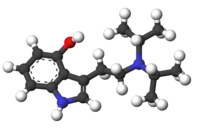

4-Hydroxy-N,N-diisopropyltryptamine (4-HO-DiPT or Iprocin) is a synthetic psychedelic drug. It is a higher homologue of psilocin, 4-HO-DET, and is a positional isomer of 4-HO-DPT and has a tryptamine molecular sub-structure.

| 3D model (JSmol) | |